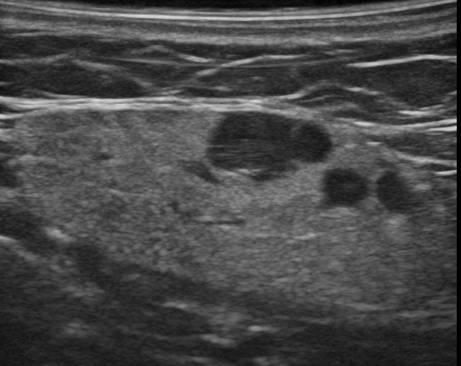

Hạch tuyến nước bọt

» Thông tin: Nữ giới – 66 tuổi.

» Lâm sàng: Sưng đau vùng góc hàm.

# Hạch lành tính ngoại vi tuyến nước bọt dưới hàm.